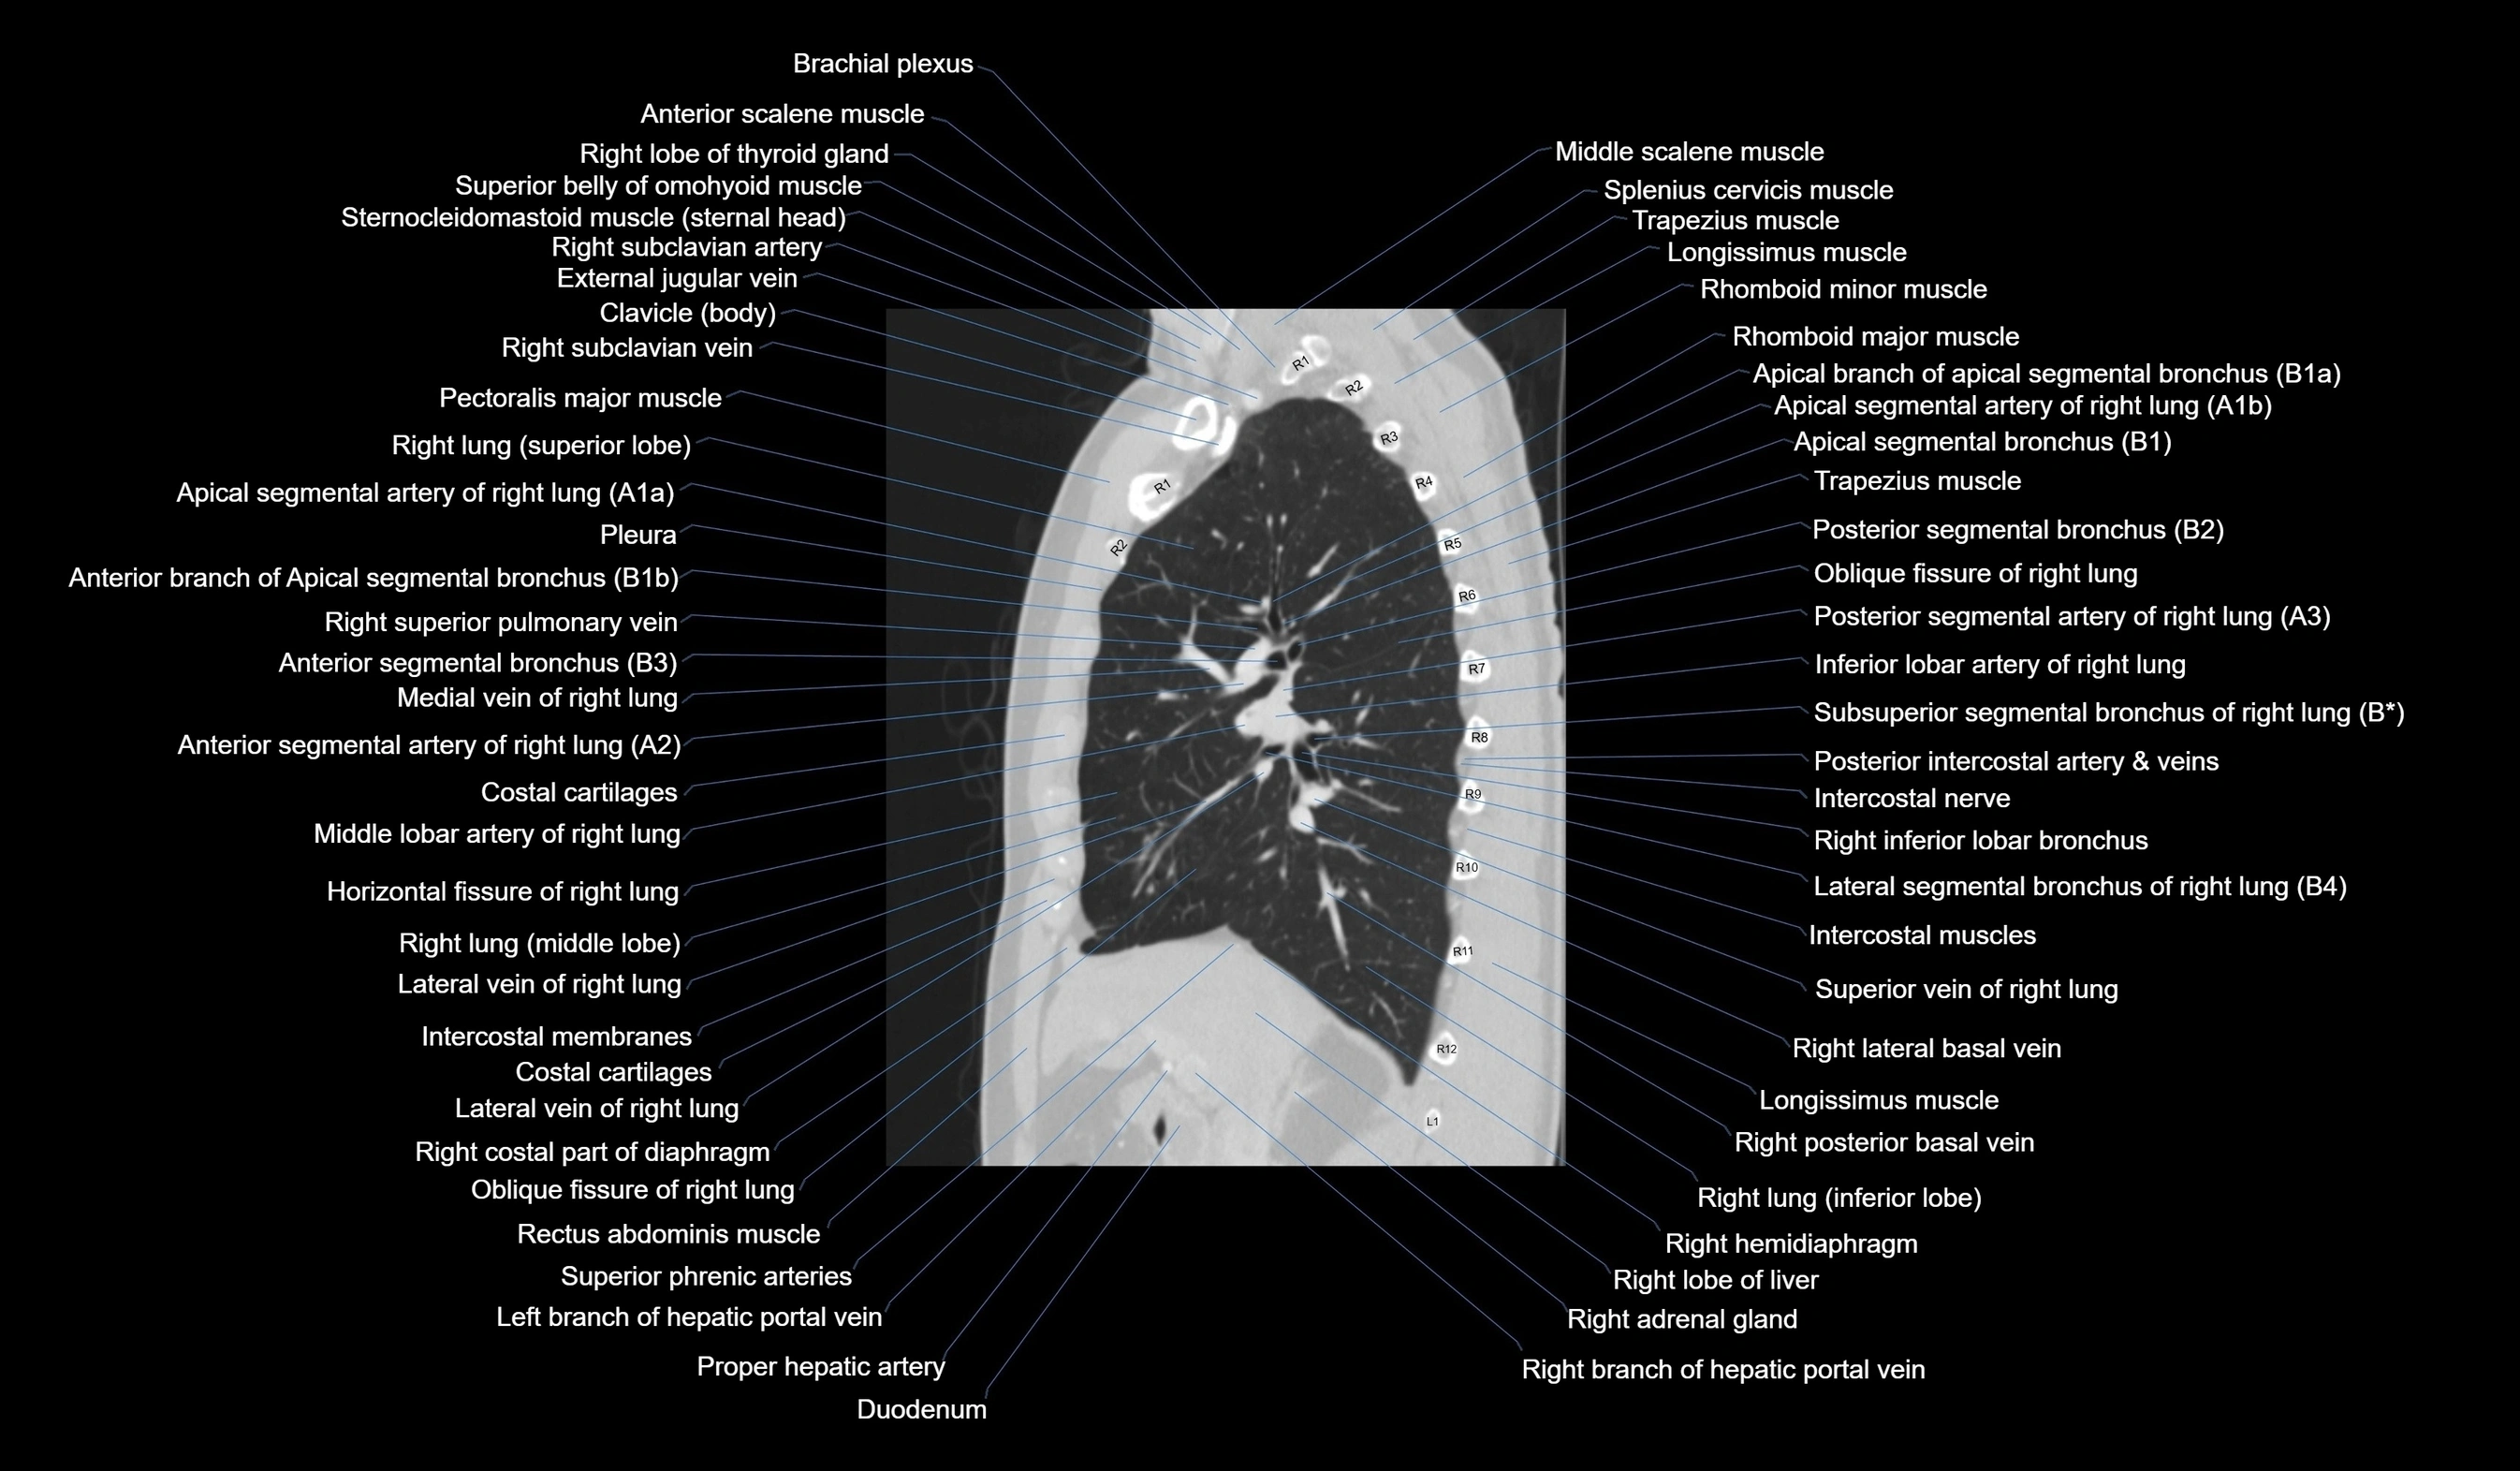

- Apical segmental artery of right lung

- Apical segmental bronchus of right lung

- Inferior lobar artery of right lung

- Lateral vein of right lung

- Medial vein of right lung

- Middle lobar artery of right lung

- Oblique fissure of right lung

- Posterior segmental artery right lung

- Posterior segmental bronchus of right lung

- Right inferior lobar bronchus

- Right lung (inferior lobe)

- Right lung (middle lobe)

- Right lung (superior lobe)

- Subsuperior segmental artery of right lung

- Superior segmental artery of right lung

- Superior segmental bronchus of right lung (B6)

- Superior vein of right lung